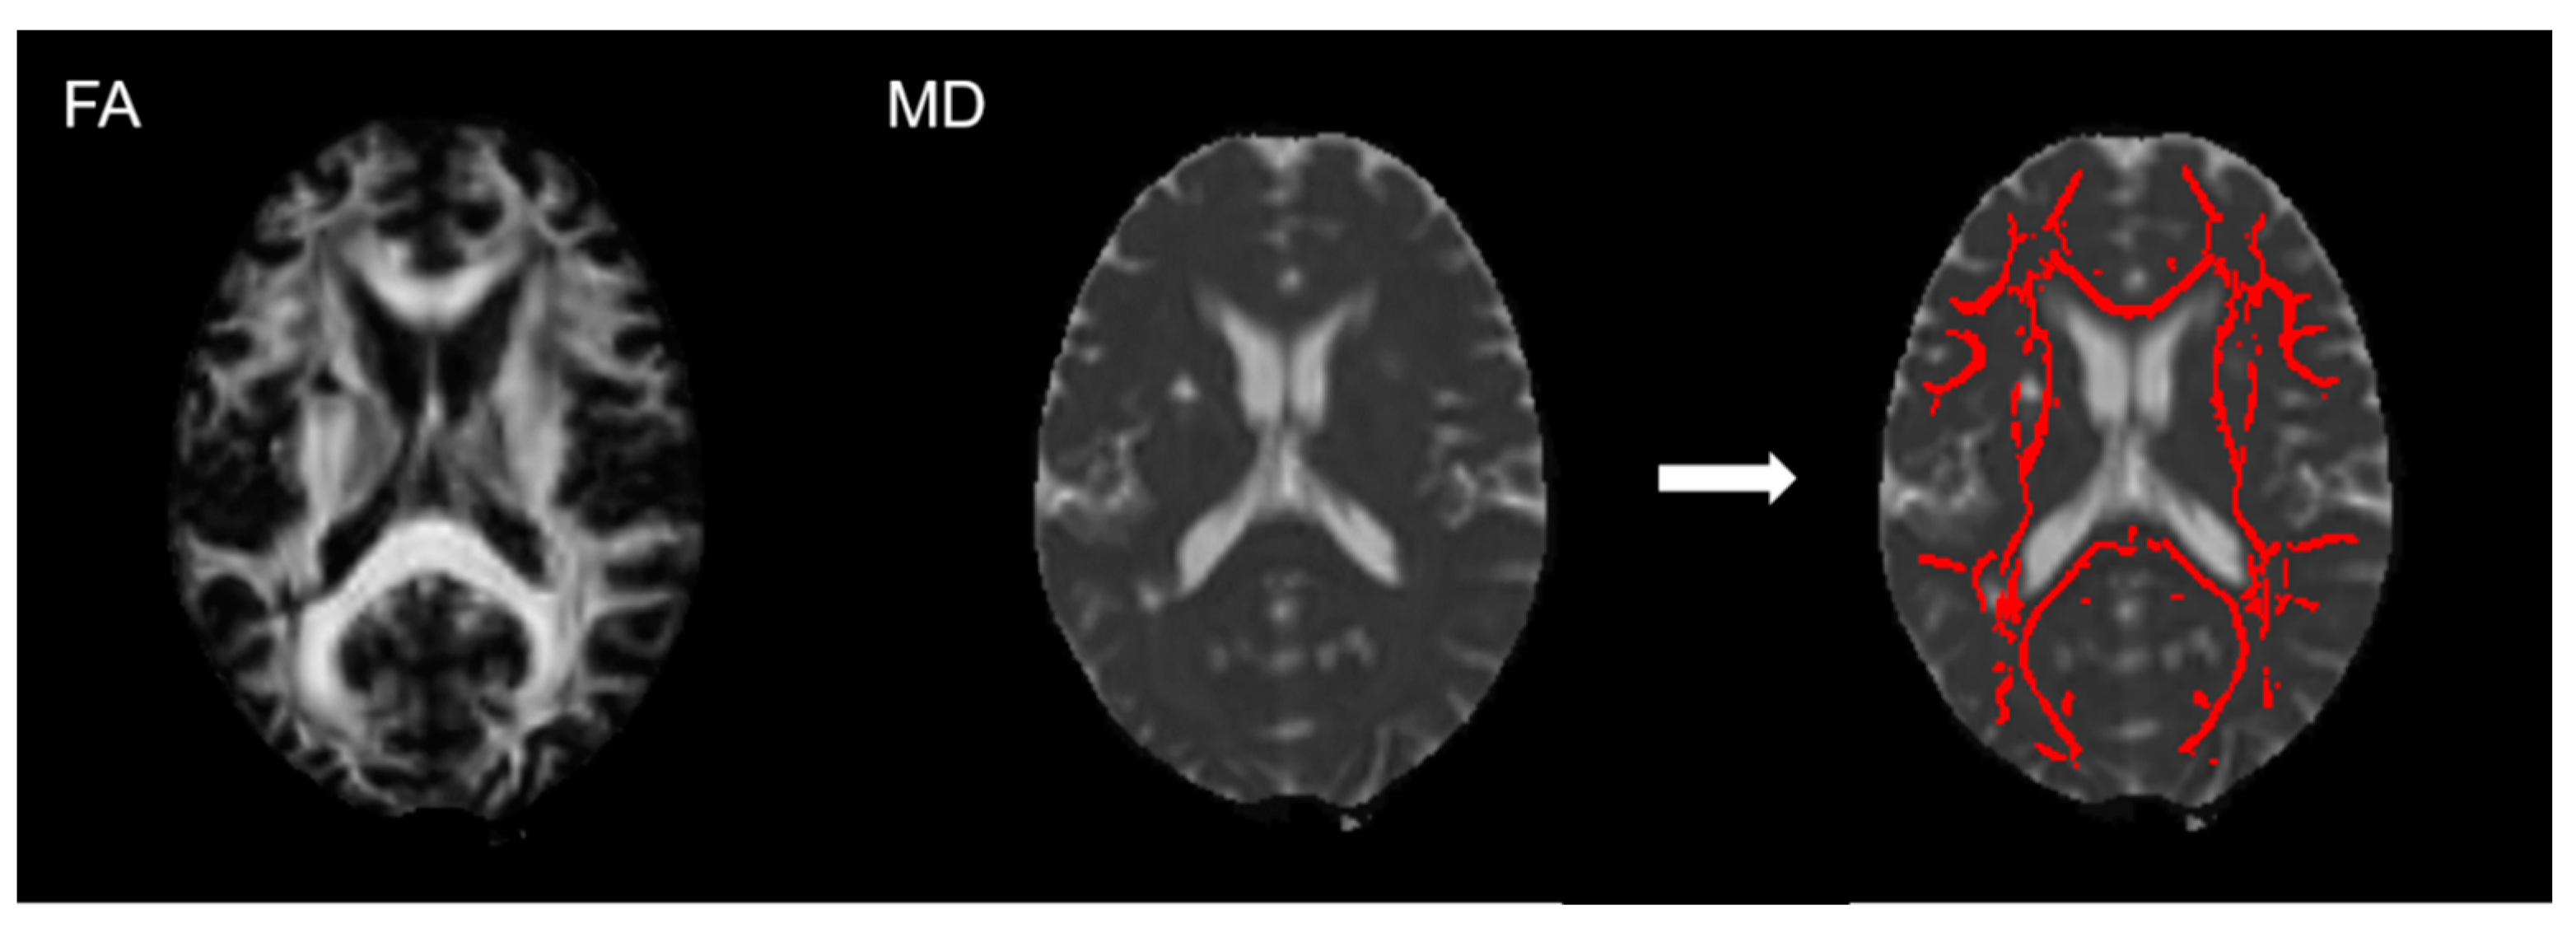

2.4. Imaging Analysis